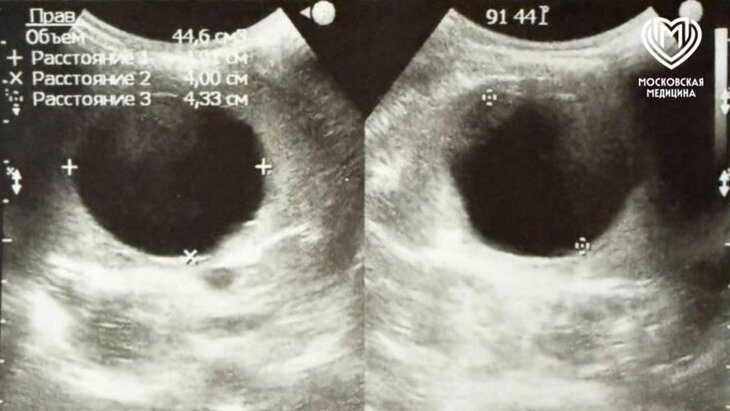

Хирурги Детской городской клинической больницы № 9 имени Сперанского удалили шестилетней девочке кисту, занимавшую большую часть селезенки. Об этом сообщила пресс-служба департамента здравоохранения Москвы.

"Исследования брюшной полости показали: киста занимает две трети селезенки и располагается возле крупных магистральных сосудов, которые кровоснабжают орган", – говорится в сообщении.